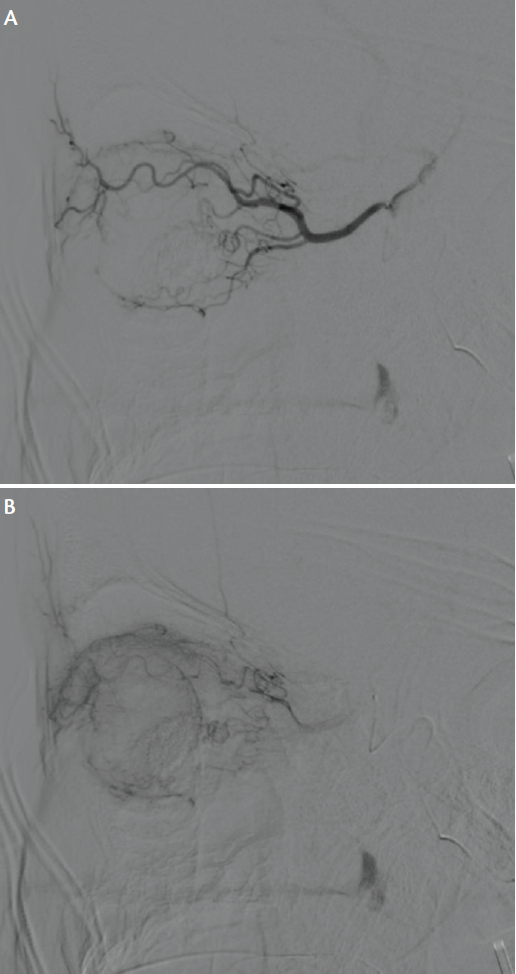

Figure 3. Image of superselective microcatheter injection (early phase) demonstrating opacification of the left ophthalmic artery, lateral view (A). Superselective microcatheter injection (late phase) demonstrating opacification of the ophthalmic artery, lateral view. The choroidal blush and the shadow of the globe and orbital structures are well visualized (B).

Melphalan is the primary chemotherapeutic agent for IAC, but topotecan or carboplatin can be administered along with or instead of melphalan, depending on the patient’s previous therapeutic history and his or her response to each drug (Figures 1 and 2). Chemotherapeutic drugs are diluted with 20 mL to 30 mL saline and are injected through a 1-cc microsyringe in a repetitive, pulsatile manner over 30 minutes for homogeneous drug delivery. After the injection, a superselective ophthalmic artery angiogram is performed through a microcatheter to verify patency of the artery (Figure 3), followed by an angiogram performed through a guide catheter in the internal carotid artery to evaluate the intracranial vasculature distally.